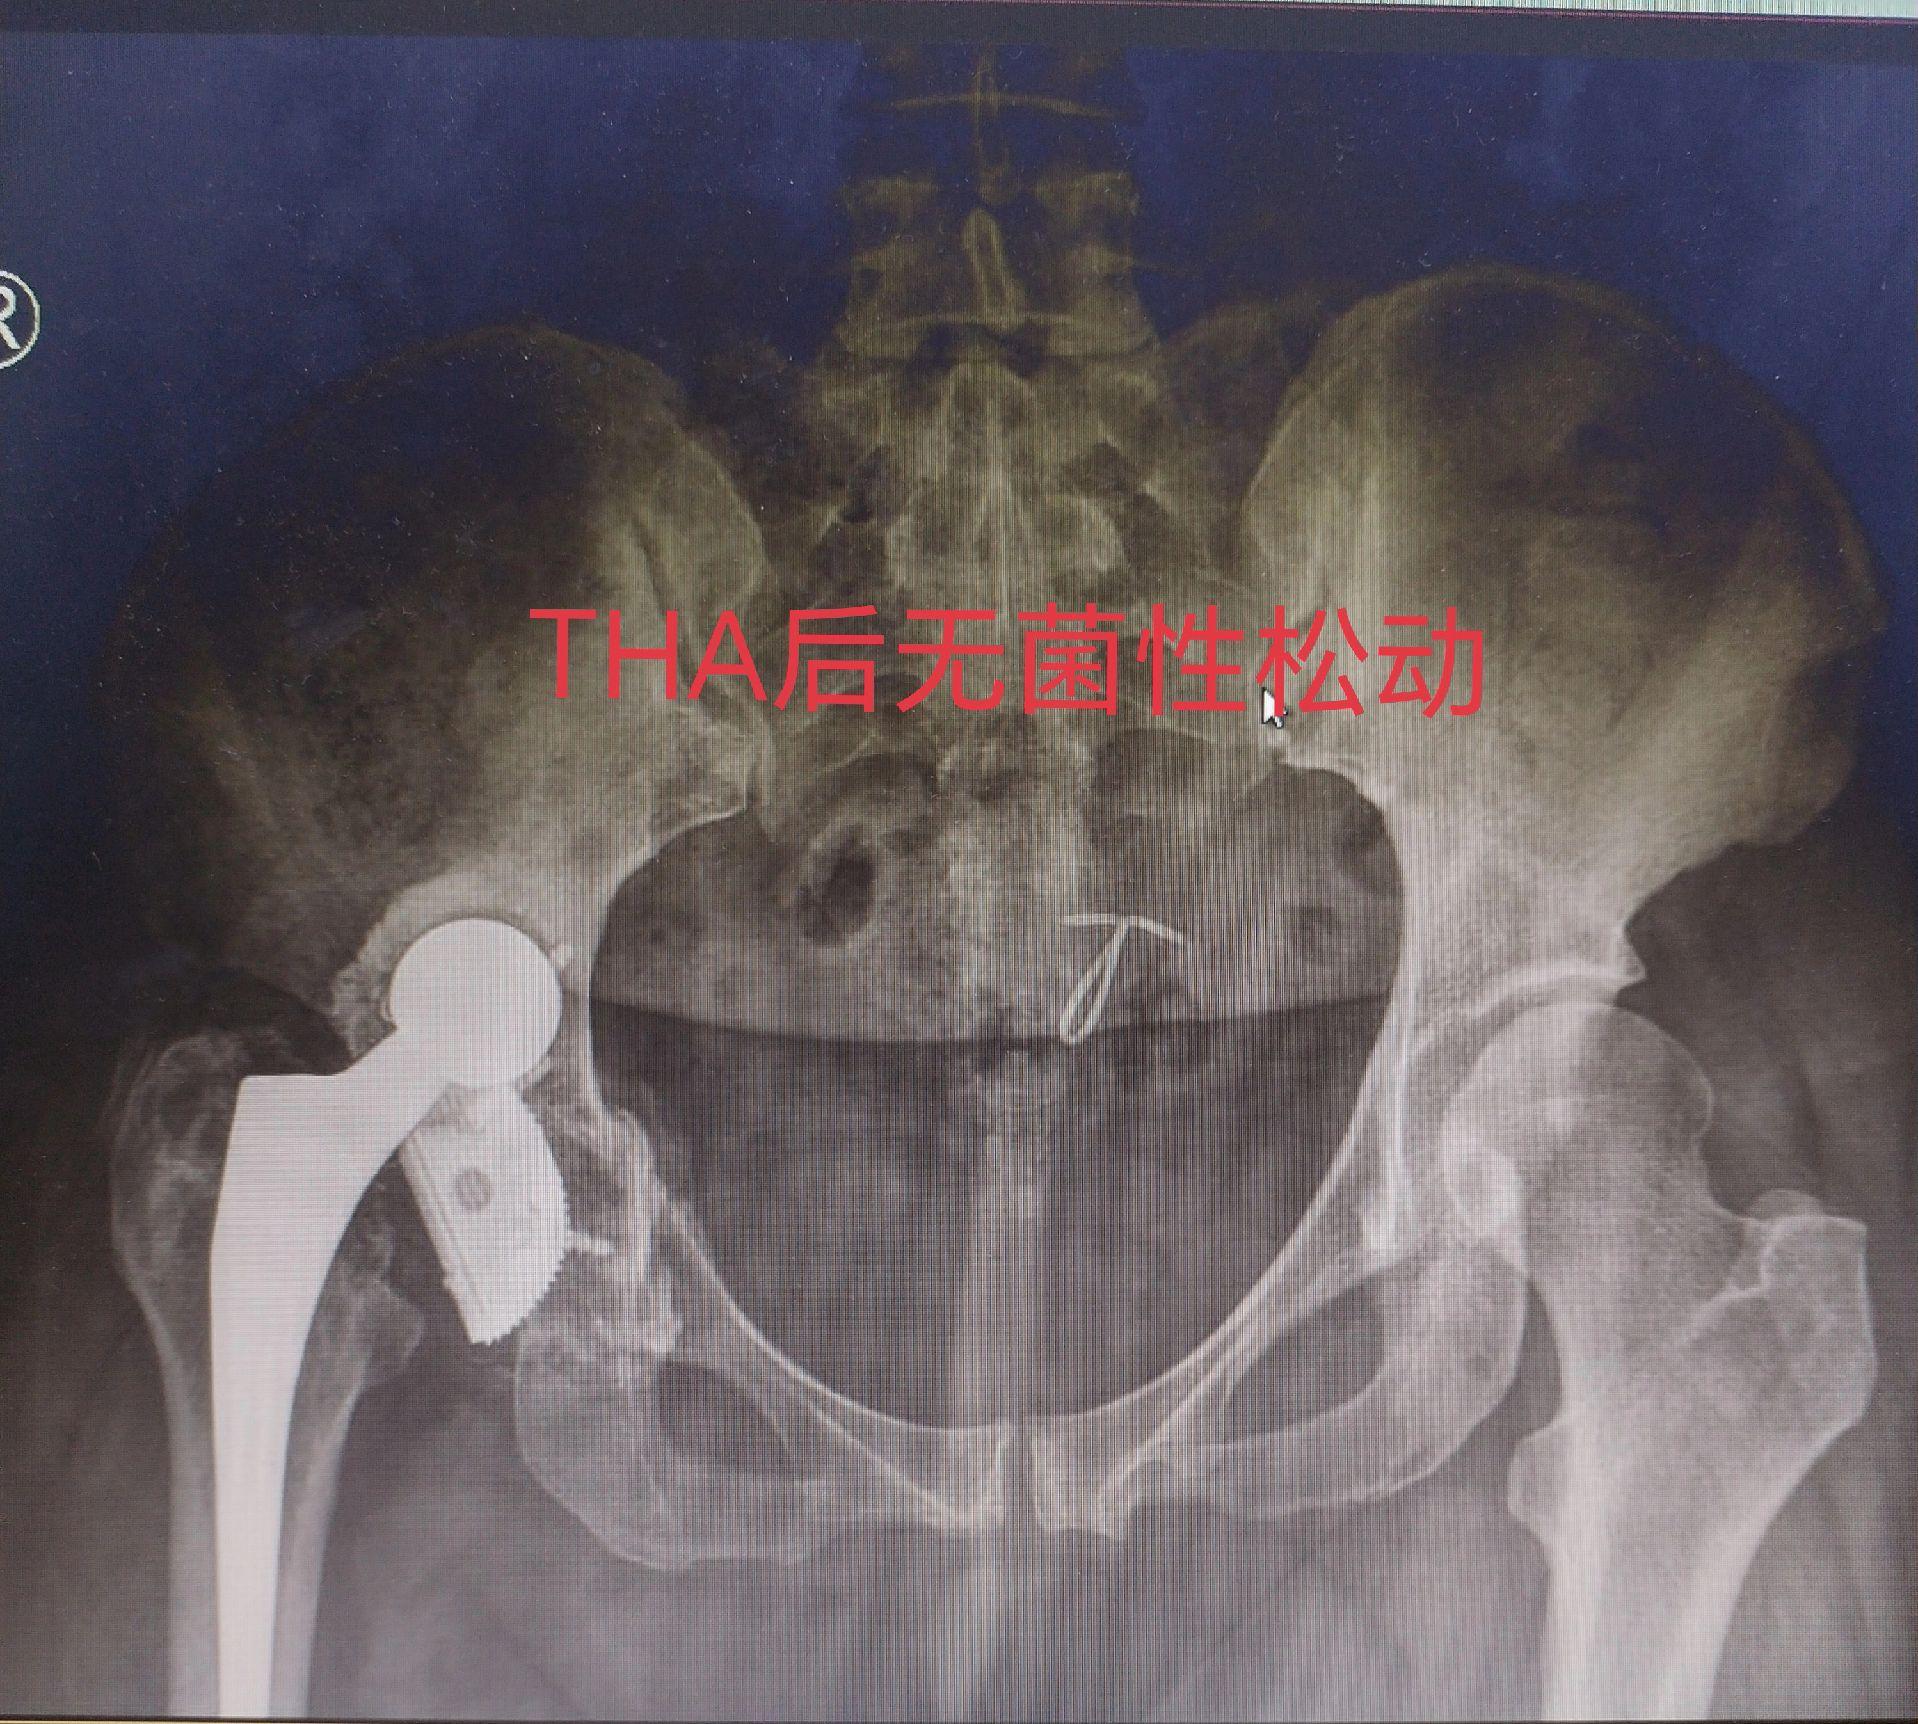

髋关节翻修术。髋关节置换术后假体磨损导致松动,一期翻修,只要重建的牢固,一样可以两天下床走路。愿每一个病人都能快速康复🌹关节置换